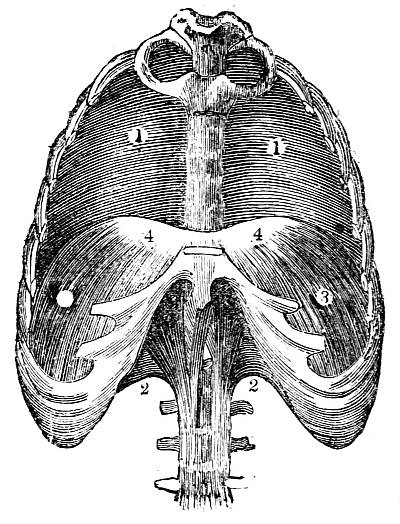

Fig. CXXXIV.—

View of the Respiratory Apparatus in

Man.

1. The Trachea. 2. The right lung. 3. The left lung.

4. Fissures, dividing each lung into, 5. Large portions

termed lobes. 6. Smaller divisions termed lobules. 7.

Pericardium. 8. Heart. 9. Aorta. 10. Diaphragm separating

the cavity of the thorax from that of the abdomen.

357. In man there are two pulmonary bags (fig.

CXXXIV. 2, 3), of nearly equal size, which, together

with the heart, completely fill the large cavity

of the thorax (fig. CXXXIV.), their external surface

being everywhere in immediate contact with

the thoracic walls. One of these bags is placed on

the right side of the body, constituting the right

lung (fig. CXXXIV. 2), and the other on the left,

constituting the left lung (fig. CXXXIV. 3). Each

lung is divided by deep fissures, into large portions

called lobes (figs. CXXXIV. 4, and CXXXV.

6), of which there are three belonging to the

right, and two to the left lung. Each lobe is

subdivided into innumerable smaller parts termed

lobules (figs. CXXXIV. 6, and CXXXV. 6), while the

lobules successively diminish in size until they

terminate in minute vesicles that constitute the

great bulk of the organ (fig. CXXXV. 8).